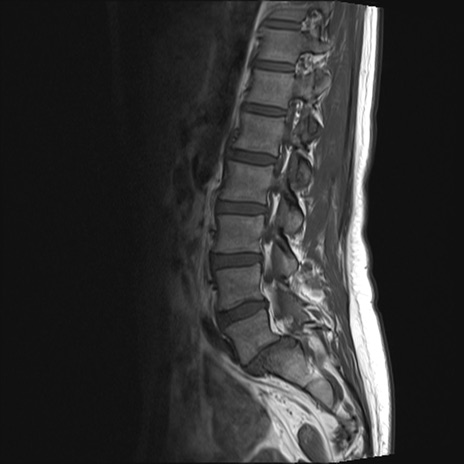

【整形】TIPS症例4 腰椎MRI T1WI(矢状断像)

腰椎MRI

T2WI(矢状断像)